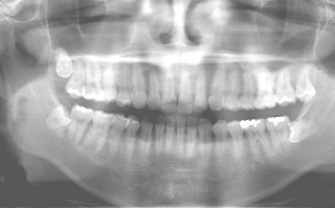

BioNaシミュレーション画像